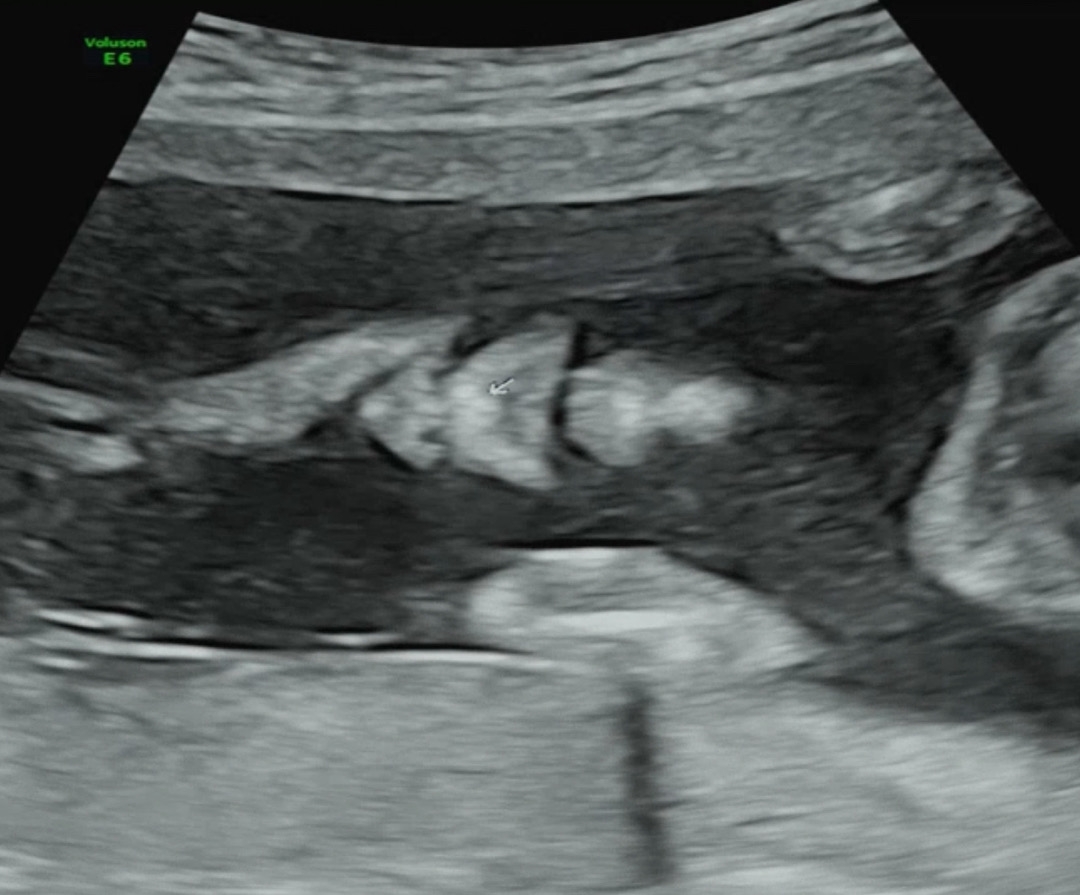

정밀 초음파 왜케 귀엽죠ㅋㅋ

어제 정밀초음파 했는데 찌부된 코랑 입이 넘 귀여워옄ㅋㅋㅋ 선생님이 돈꼬도 보여줬는데 싱기방기><